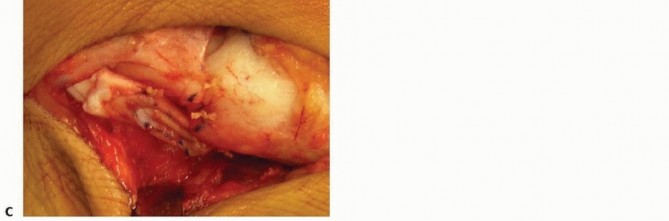

Calcaneal Osteotomy Exposure and Lateral Soft Tissue ReleasesMake a modified Ollier incision over the sinus tarsi in a Langer skin line from the superficial peroneal nerve to the sural nerve ( TECH FIG 1A).Elevate the soft tissues from the sinus tarsi. Avoid exposure of, or injury to, the capsule of the calcaneocuboid joint.Release the peroneus longus and the peroneus brevis from their tendon sheaths on the lateral surface of the calcaneus ( TECH FIG 1B).Resect the tendon sheath septum between the tendons and, if large, the peroneal tubercle. Z-lengthen the peroneus brevis tendon. Do not lengthen the peroneus longus ( TECH FIG 1C).Divide the aponeurosis of the abductor digiti minimi transversely approximately 2 cm proximal to the calcaneocuboid joint ( TECH FIG 1C).

TECH FIG 1 • A. Modified Ollier incision marked in a Langer skin line halfway between the tip of the lateral malleolus and the beak of the calcaneus (

two dots

) and extending from the superficial peroneal nerve (

dotted line

) to the sural nerve. B. The peroneus brevis (

above

) and the peroneus longus (

below

) have been released from their tendon sheaths. C. The soft tissue contents have been elevated from the isthmus of the calcaneus. The peroneus brevis is lengthened, and the peroneus longus is retracted. The aponeurosis of the abductor digiti minimi is exposed for release. D-F. Finding the interval between the anterior and middle facets of the subtalar joint. D. A Freer elevator is inserted perpendicular to the lateral border of the calcaneus just proximal to the beak of the calcaneus. It makes contact with the middle facet.E. The Freer is rotated distally until the tip falls into the interval between the anterior and middle facets. F. This is confirmed with the mini-fluoroscope. (From Mosca VS. Calcaneal lengthening osteotomy for valgus deformity of the hindfoot. In: Tolo V, Skaggs D, eds. Master Techniques in Orthopaedic Surgery: Pediatric Orthopaedics. Philadelphia: Lippincott Williams & Wilkins, 2008:263-276.)Identify the interval between the anterior and middle facets of the subtalar joint with a Freer elevator. Insert it into the sinus tarsi perpendicular to the lateral cortex of the calcaneus at the level of the isthmus (ie, the lowest point of the dorsal cortex of the calcaneus proximal to the beak and distal to the posterior facet) ( TECH FIG 1D). The middle facet will be encountered.Slowly angle the Freer distally until it falls into the interval between the anterior and middle facets ( TECH FIG 1E).Confirm that the Freer is in the interval using fluoroscopy ( TECH FIG 1F).Replace the Freer with a curved Joker elevator. Place a second Joker elevator around the plantar aspect of the calcaneus in an extraperiosteal plane in line with the dorsal Joker.Remove the Jokers and prepare the exposures for the other procedures before performing the calcaneal osteotomy. 1. ##